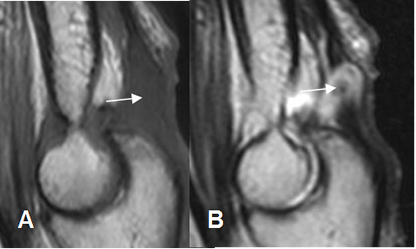

Fig 41. Ruptura del tríceps.

A: RM sagital en T1 y B: RM sagital T2. Ruptura del tendón ddel tríceps, con espacio lleno de líquido entre los extremos. (Flechas).